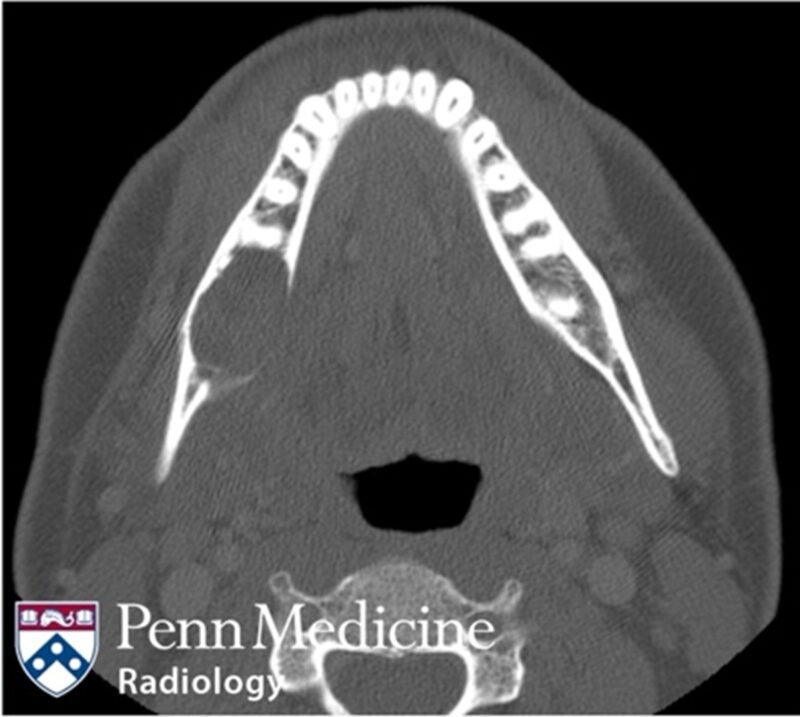

52-year-old woman with vertigo and sinus congestion

A 52-year-old female presented to the emergency department for vertigo and sinus congestion.

Published Date: February 5, 2026

Tags:

CT

,

Head and Neck

MRI

PET